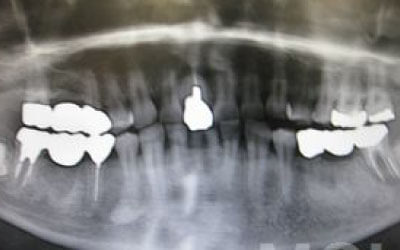

1)ブリッジ

2)歯を大きく削る+支えの歯に1.5倍の力がかかる

3)前後の歯の寿命が著しく減る

ブリッジの支えの歯は、データでは10年以内に68%が抜歯になります。